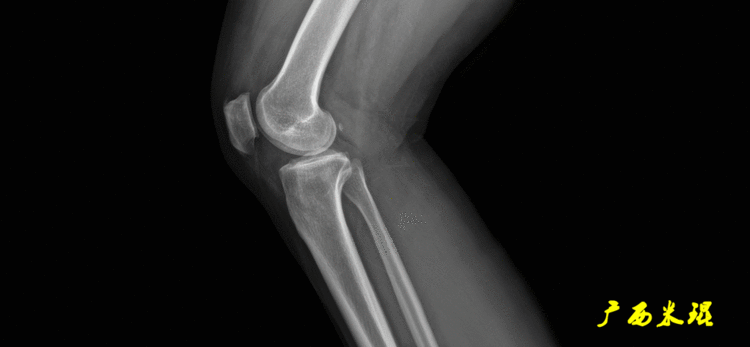

患者直立于摄影架上,后背贴近摄影架,双手自然下垂,膝关节尽量伸直,足部与双肩同宽,要求投照时双髌骨朝正前方,通常患者双足尖应平行向前即可。

提醒一下大家,拍摄过程中应避免下肢的外旋和内旋。如果有一侧肢体短缩时,投照应当用脚垫垫高短缩肢体,使骨盆保持水平,这样下肢短缩测量才精确。如果有肢体旋转畸形时,还是以髌骨朝前为标准,虽然此时双足可能不能保持平行。